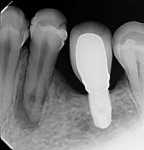

During the second session, the root canal dressing was removed, and the canals were irrigated again using the following protocol. First, 3 mL of 2.5% NaOCl solution was introduced and agitated for 60 seconds with a rotary plastic activating file (Bassi Clean™, Bassi Endo) at 20,000 rpm. Next, 1 mL of 17% EDTA was placed and agitated for 60 seconds at 20,000 rpm. And last, another 3 mL of 2.5% NaOCl solution was placed and agitated for 60 seconds at 20,000 rpm, followed by a final irrigation with 1 mL of saline solution. After the canals were properly dried with absorbent paper cones, the root canal obturation was performed with a bioceramic root canal sealer (BIO-C® Sealer, Angelus) and gutta-percha using the lateral condensation technique (Figure 2 and Figure 3). The tooth received a fiberglass post in the distal canal and was restored with composite resin. At the 6-month follow-up visit, the patient was asymptomatic, and complete healing of the periapical tissues was observed (Figure 4).